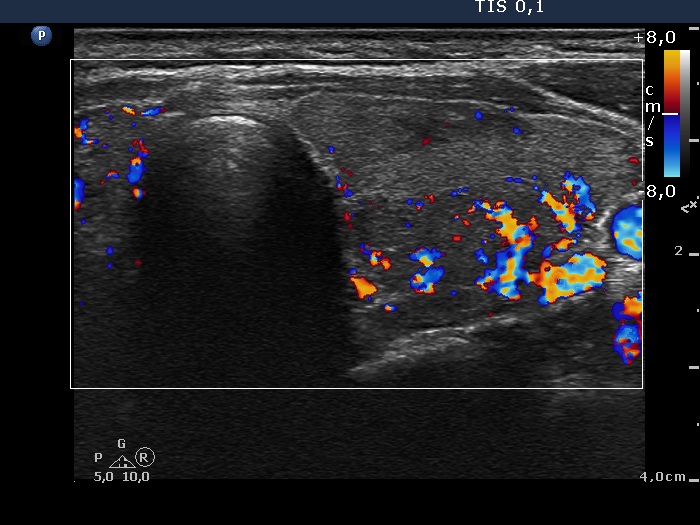

Consecutively operated patients with autoimmune thyroid disease - case 19 (1771) (ultrasonographic picture 8)

Lower part of the left lobe, transverse scan, color Doppler mode. The moderately hypoechogenic area presents an irregularly increased vascularization.